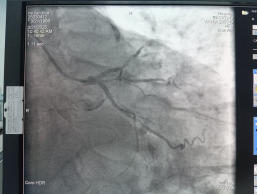

入住我院心血管内科后,医生们做了全面细致的术前评估,并于3月1日为其做了冠脉造影术。检查结果显示:左前降支近段最严重狭窄90%,第一对角支最严重狭窄95%,回旋支中段闭塞,右冠近段最严重狭窄80%。结合患者症状及心电图表现,决定先处理回旋支病变。

经过反复研读影像,制定周全手术预案。王伴主任团队顺利为患者开通闭塞的回旋支,由于血管病变时间长,存在废用萎缩的情况,决定给予药物球囊扩张介入治疗,拟1个月后再处理其他病变血管,术后第二天患者感胸闷较前明显好转。

术前 术后